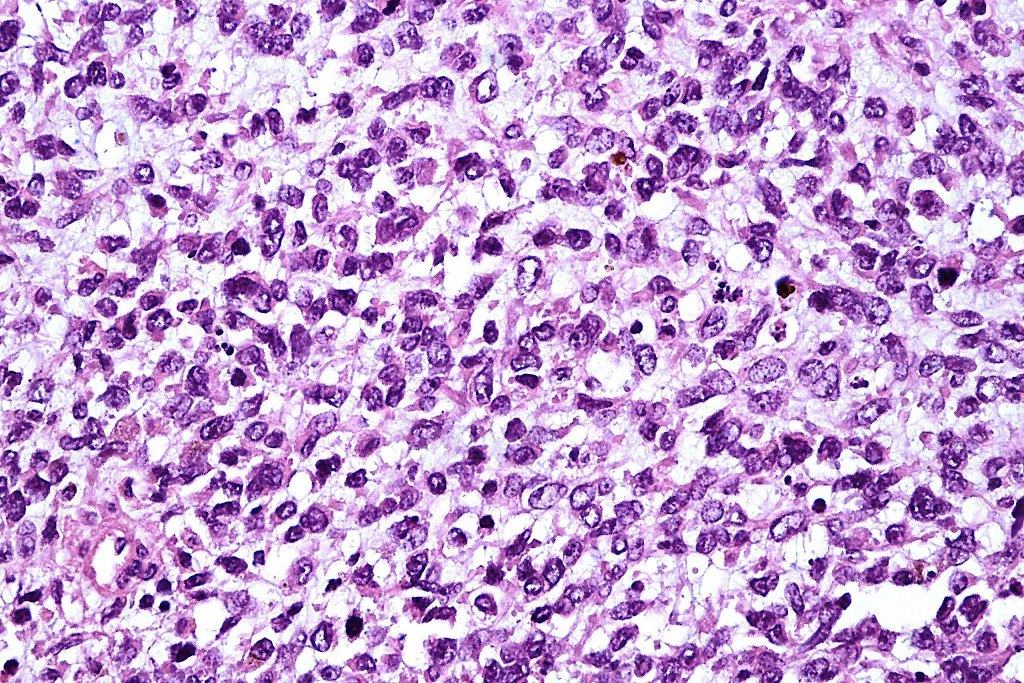

•It is hypercellular and most often composed of epithelioid cells showing little pleomorphism & only occasional mitoses

•Nuleoli are small

•Intracytoplasmic pseudo-inclusions

•The constituent cells are generally larger than the adjacent nevus cells

•Some examples show more marked pleomorphism with prominent nucleoli and increased mitotic activity but abnormal mitoses are not a feature. These are not associated with any sinister biological potential